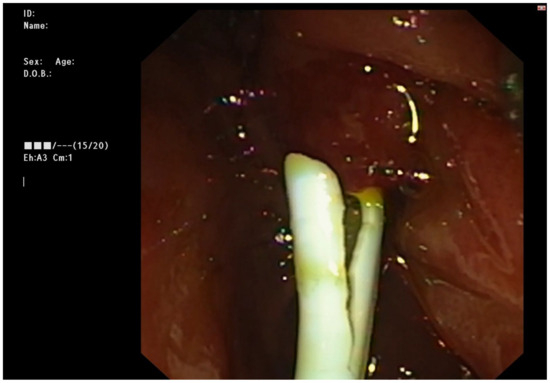

2.3. Endoscopic Management

Figure 1. Transduodenal endoscopic cannulation through the distal orifice of the hepatico-duodenal fistula.